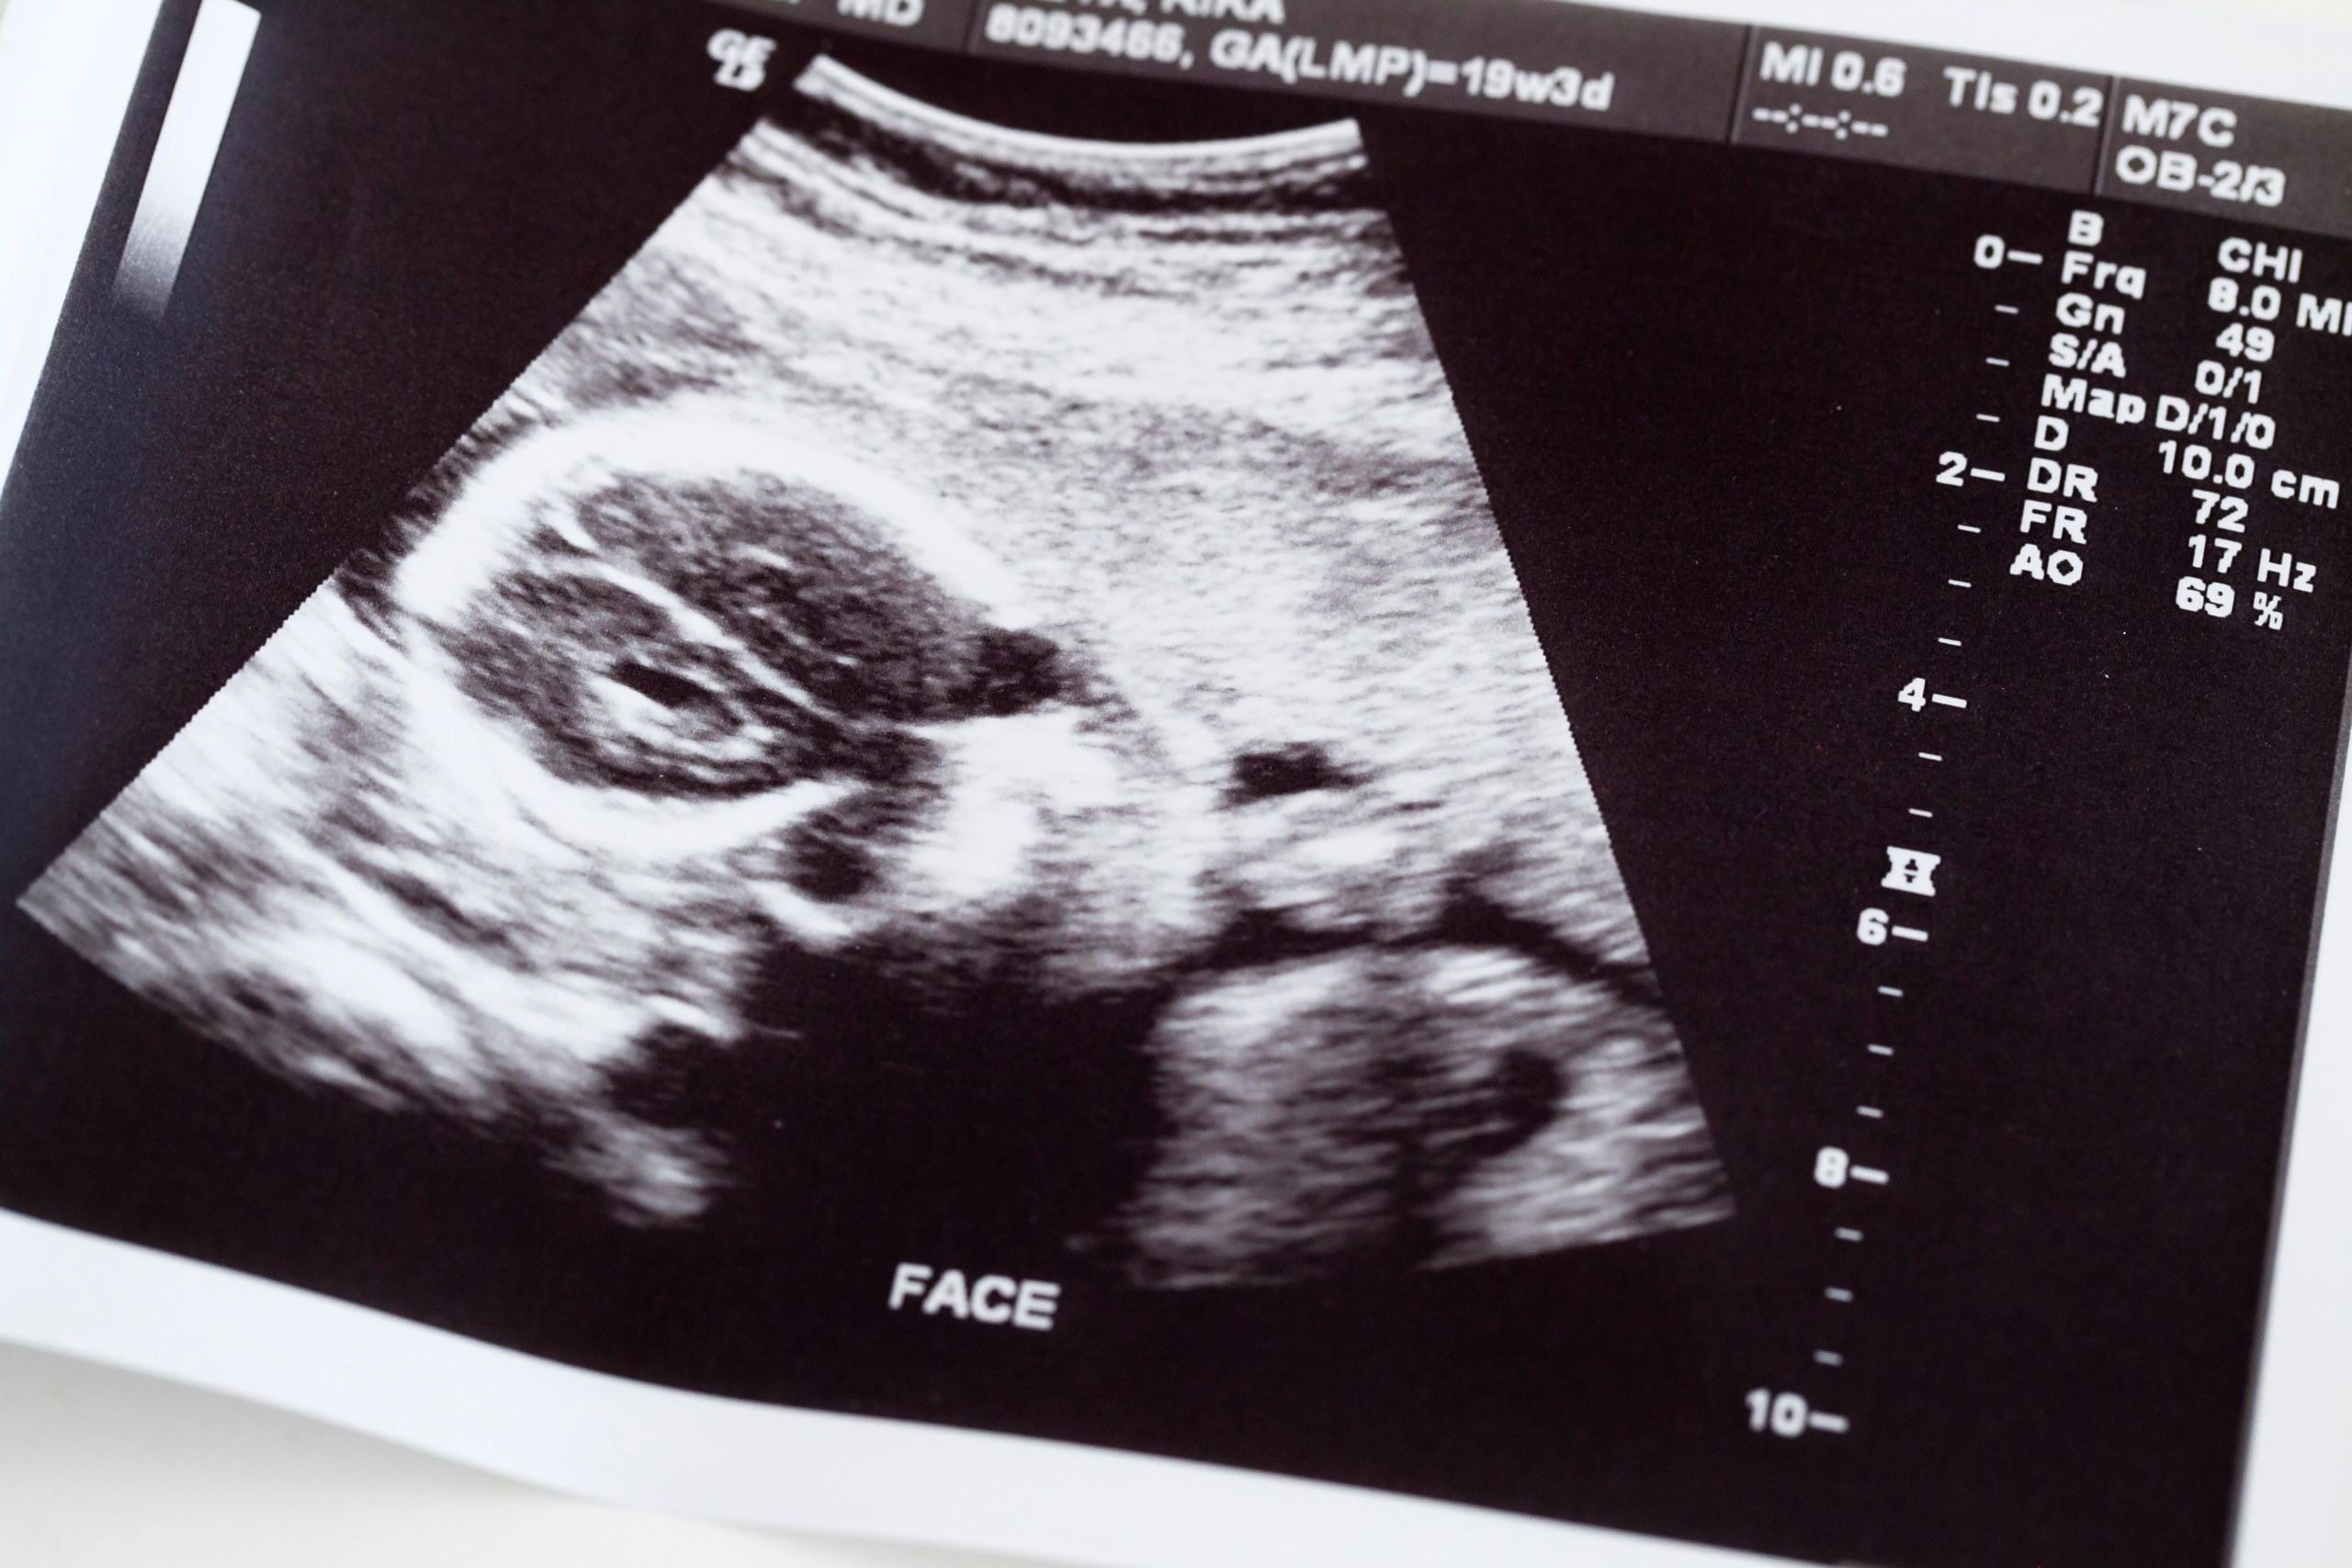

She thought her pregnancy was over. But three weeks later, the doctors discovered something unimaginable